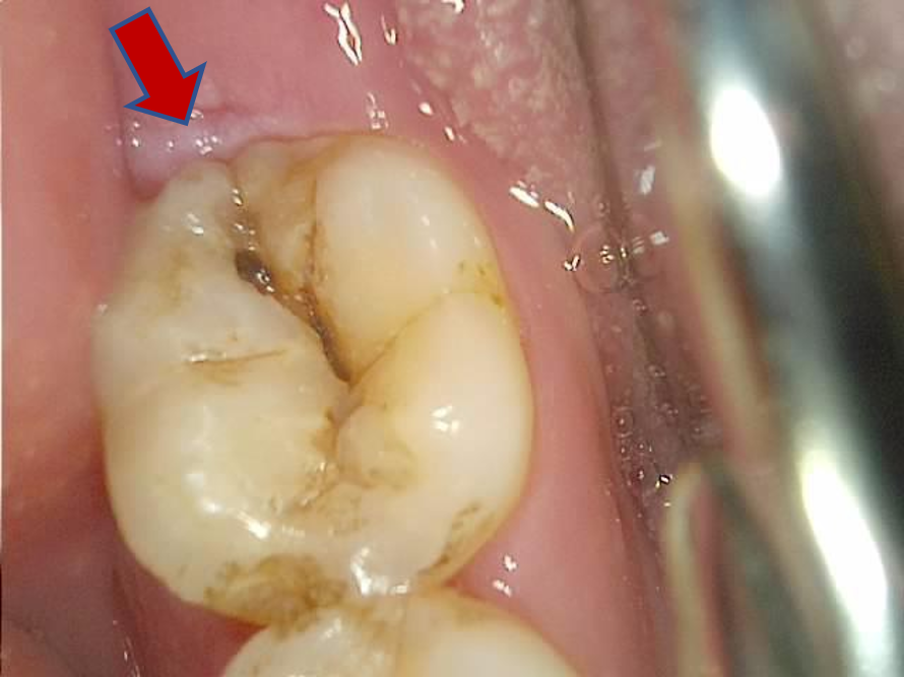

통증을 호소하시는 치아를 보면 crack이 하도 많아서 잘 구별이 되지 않지만,

아무래도 화살표의 저 crack이 결정적인 역할을 하는 것 같다.

치아에 금이 간 사진, crack

턱근육이 너무 강하셔서, 구강카메라도 간신히 찍음.. ㅜㅜ